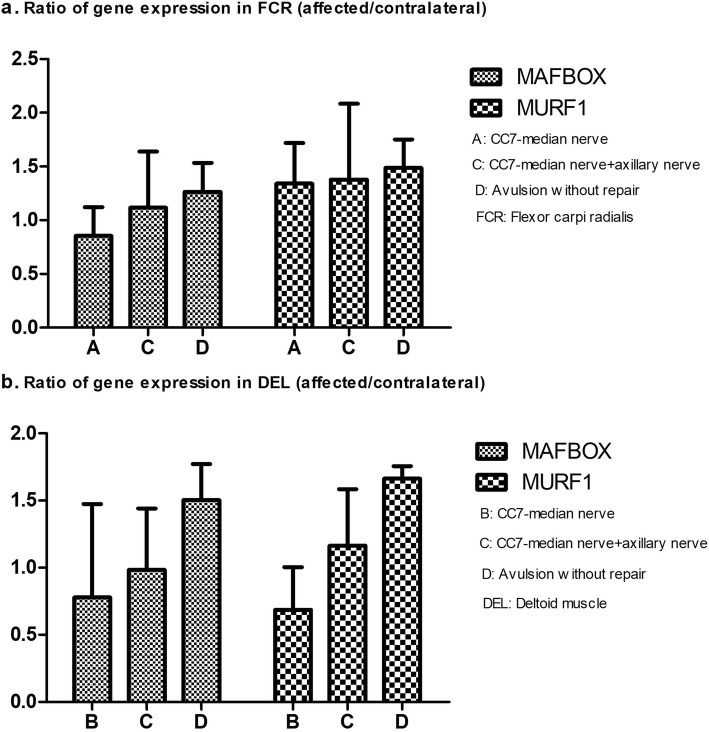

Gene expressions related to skeletal muscle atrophy

A previous study was reported [5] that Muscle RING Finger 1(MuRF1)and Muscle Atrophy F-box (MAFbx)were the genes related to skeletal muscle atrophy. They were positively correlated with muscle atrophy. In Group A and B, FCR and DEL were biopsied respectively. Both of the two muscles were biopsied in Group C and D. Muscle tissue samples were dissolved in TRIzol™ (1600 Faraday Ave, Carlsbad CA92008 USA). Then DNA was separated, precipitated and extracted from the samples. The purity of the DNA was determined. Expression of each gene was assayed by RT-qPCR (Agilent Technologies, Inc., Santa Clara, CA, USA). The relative expression levels of the two genes were determined using 2-ΔΔCt method.

PCR for MAFBOX and MURF1

By qRT-PCR assay, the ratio of MAFBOX expression in FCR on affected side to contralateral side successively increased from Group A to C to D, but there were no significant differences of the ratios among the three groups. The trend of MURF1 ratios in FCR from Group A to C to D was the same with that of MAFBOX ratios in FCR. (Fig. 7a).

Fig. 7.

a The ratios of gene expressions in FCR (affected/contralateral) in different groups. b The ratios of gene expressions in DEL (affected/contralateral) in different groups

As for DEL, the ratios of MAFBOX and MURF1 rose from Group B to C to D. The ratios in the three groups had no statistical differences among them, no matter for MAFBOX or MURF1. (Fig. 7b).